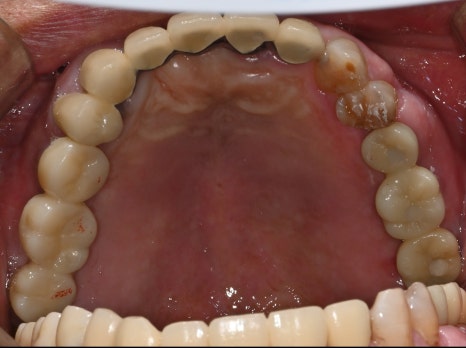

왼쪽 사진: #25-27 보철물 완성 후 촬영한 파노라마 엑스레이 입니다.

오른쪽 사진: 자연치아처럼 심미적이고 튼튼한 지르코니아로 보철 마무리 되었습니다.

🦷 이 환자분은 연세가 있으셨고, 기존 치아가 많이 닳아 치관 길이가 짧은 열악한 조건이었지만,

대표원장님의 정밀 수술과 설계로 안전하고 만족스러운 치료를 마무리할 수 있었습니다.